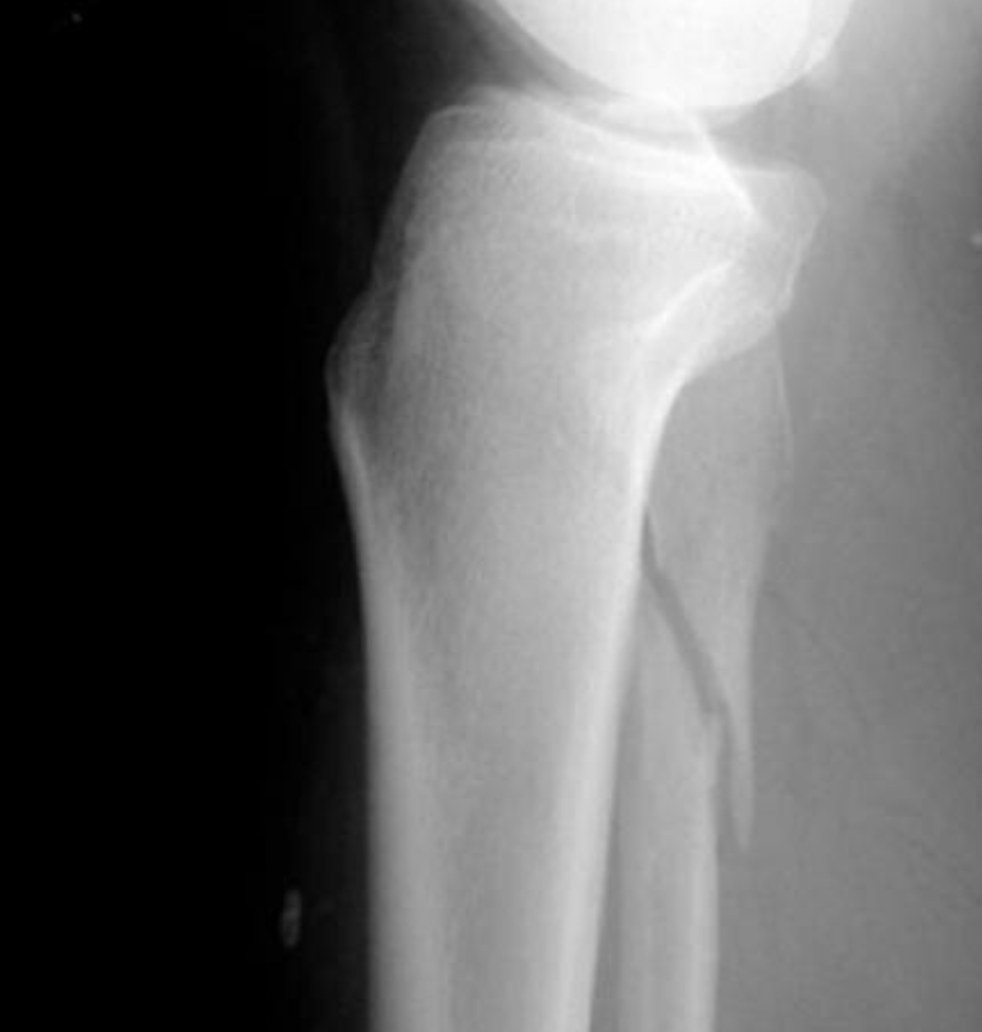

Describe the fracture seen in this X-ray [1]

Lateral tibial plateau fracture

* The fracture fragment is displaced and depressed from its normal position (dotted line)